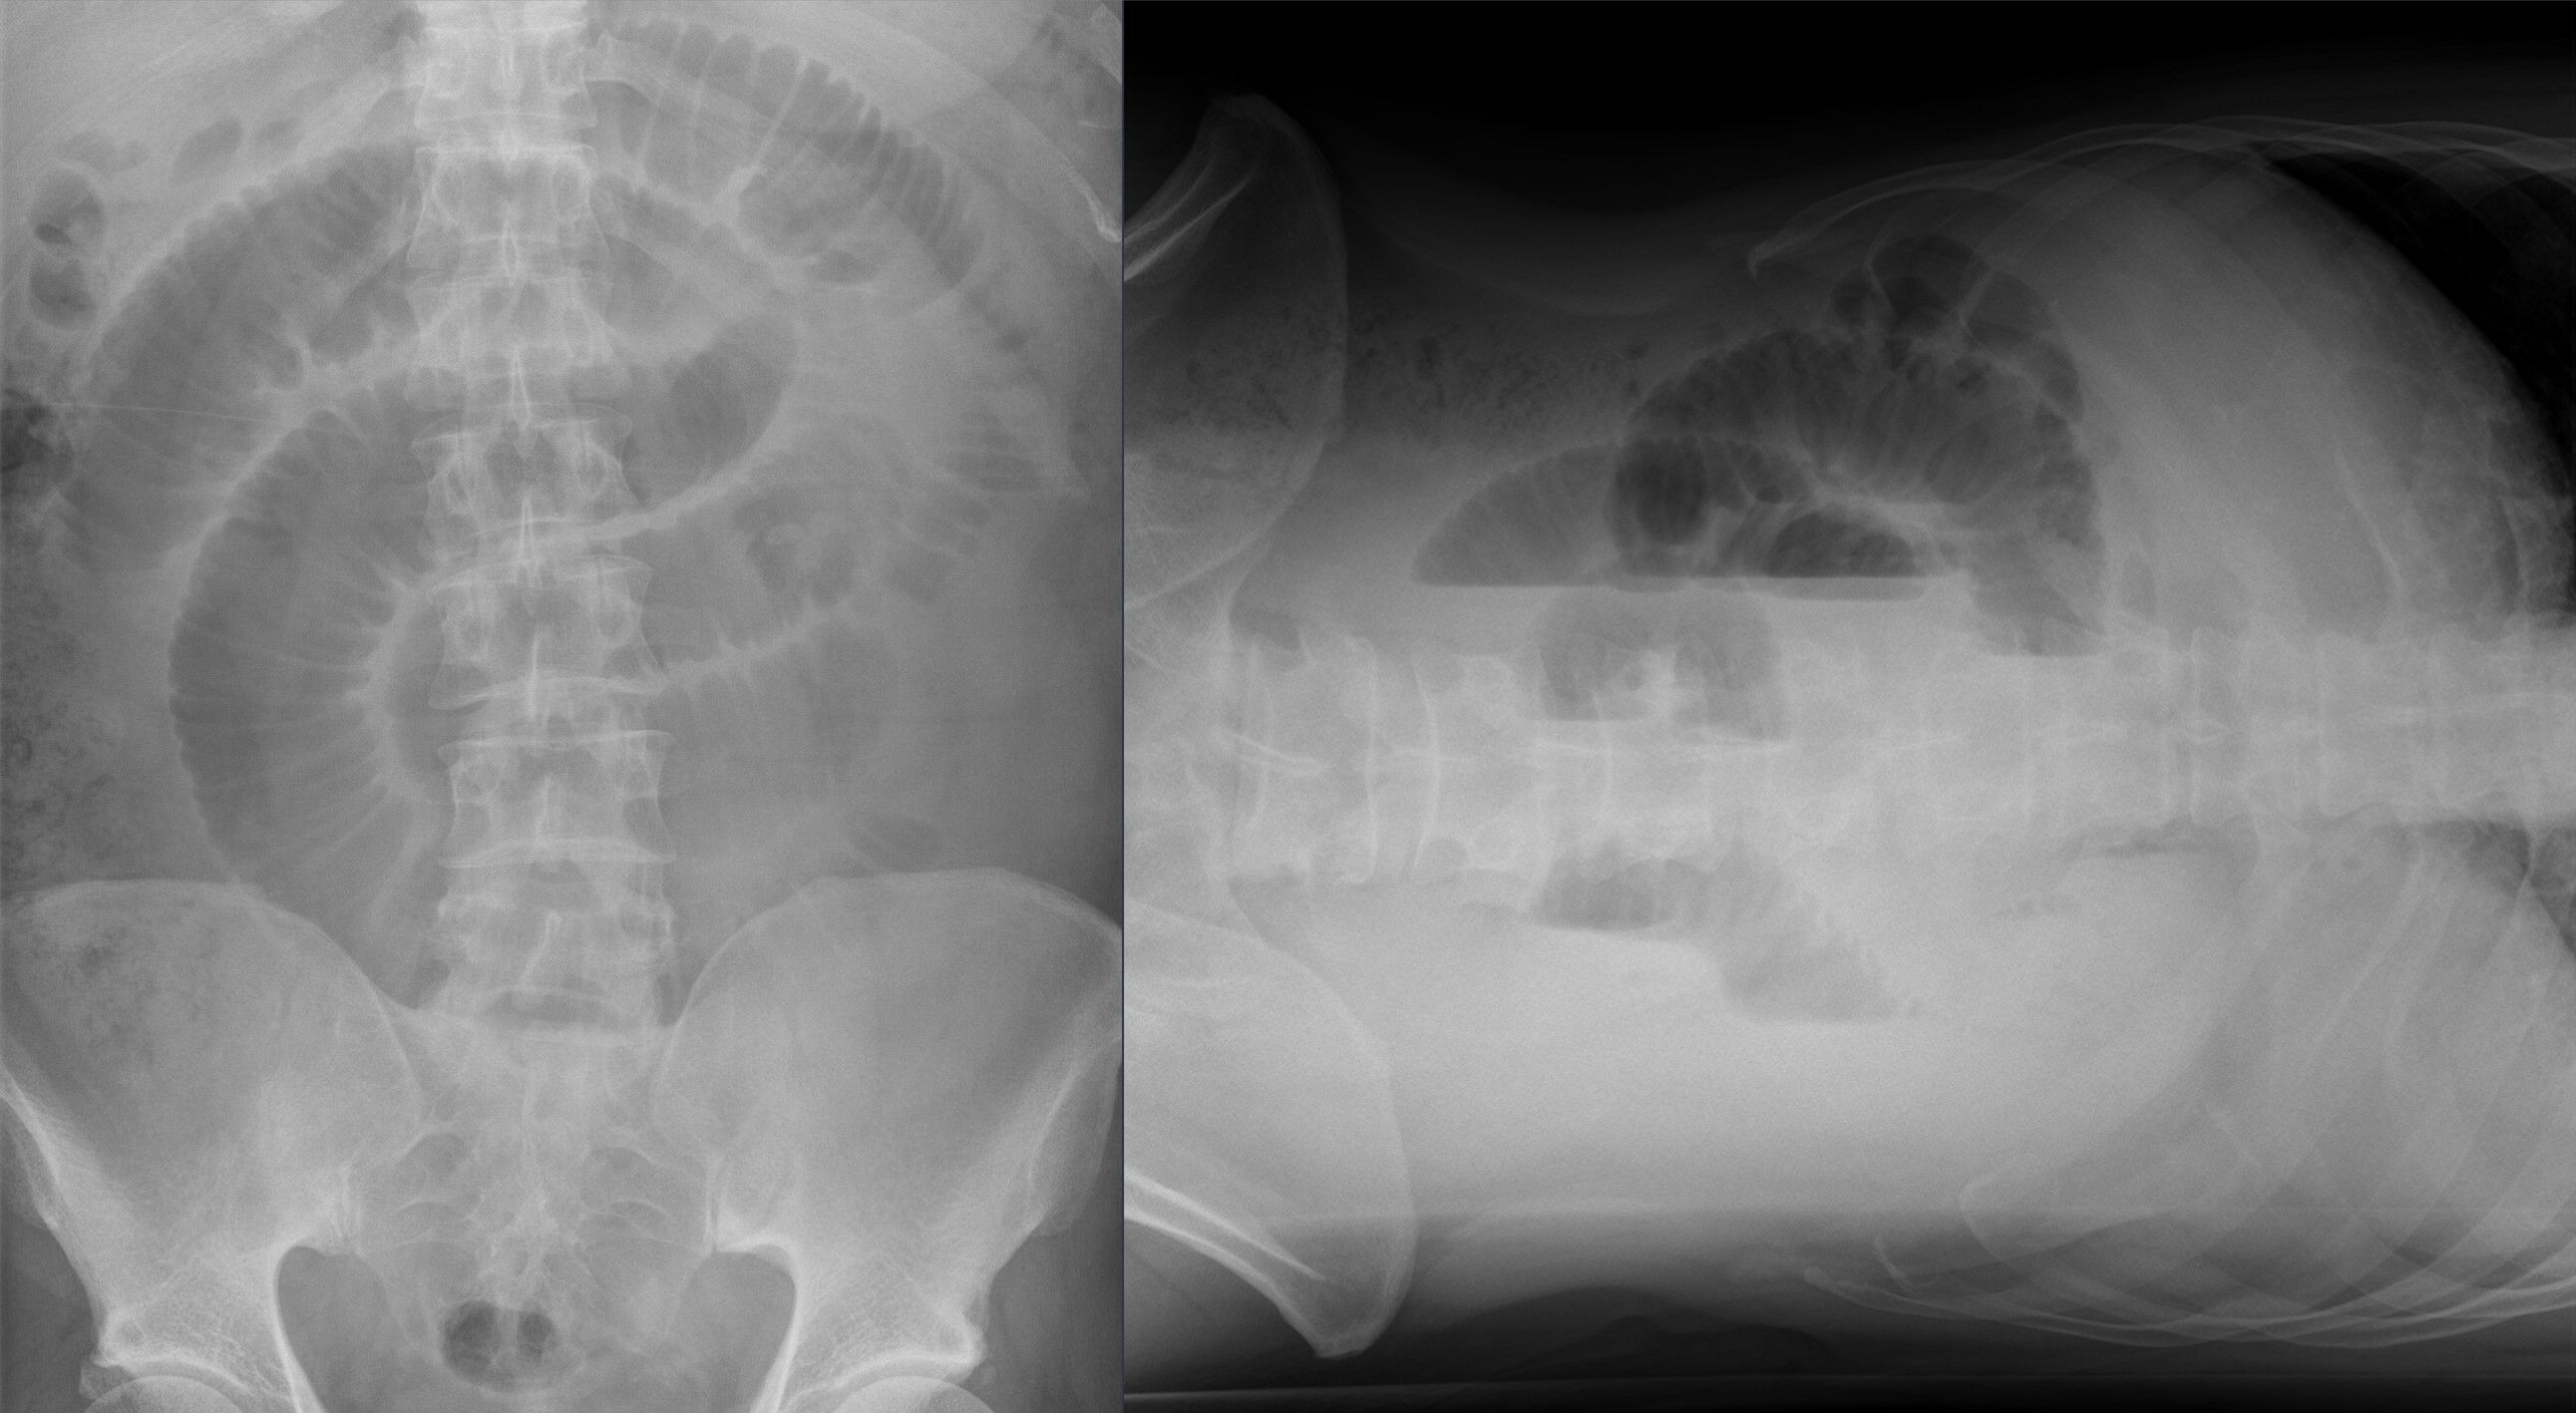

1. Die Abdomen Leeraufnahme (= konventionelles Röntgen) in Rückenlage und Linksseitenlage oder Stehend ist die 1.Wahl zur Ileus-Diagnostik

Mechanischer Dünndarmileus im Röntgenbild in 2 Ebenen. Mechanischer Dünndarmileus im Röntgenbild in 2 Ebenen.

Fig. 149 Ileus in der Bildgebung [oben: © Hellerhof, ℓ CC BY-SA 4.0; unten: © Hellerhof, ℓ CC BY-SA 3.0]#